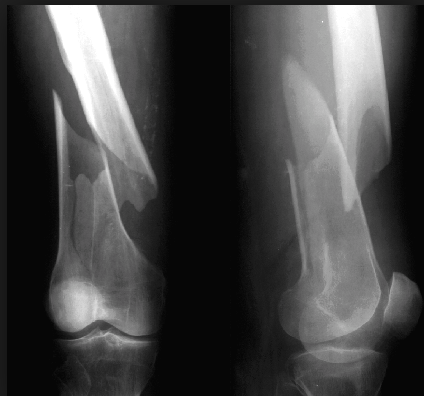

Oblique fracture

A fracture that is diagonal to a bone’s long axis

Spiral fracture

A fracture in which the bone has been twisted apart